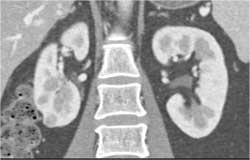

1 Cm Right Renal Cell - Easy to Miss on Arterial Phase